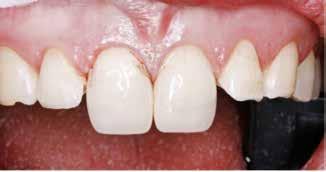

Postoperativ status

okklusal-vertikale dimension. De afficerede dentinoverflader blev ridset i overfladen med en grov diamant, men derudover blev der ikke foretaget nogen form for kavitetspræparation, da intentionen var at gennemføre en minimalt invasiv behandlingstilgang. Kofferdam blev anlagt i hvert arbejdsfelt (Fig. 3) og adhæsivet påført med en æts-og-skyl-strategi (ætsning af emalje og dentin, primer, adhæsiv). Derefter blev tænderne bygget op med en mikrohybrid komposit for at genskabe tandens naturlige form (Fig. 4). I underkæbefronten blev der kun lagt et tyndt lag med komposit pga. pladsmangel. Efter omhyggelig pudsning og polering havde patienten okklusion på samtlige tænder og var tilfreds med både funktion og æstetik.

Fig. 4. Færdigrestaurerede tænder med komposit.

Fig. 4. Final restored teeth with composite.